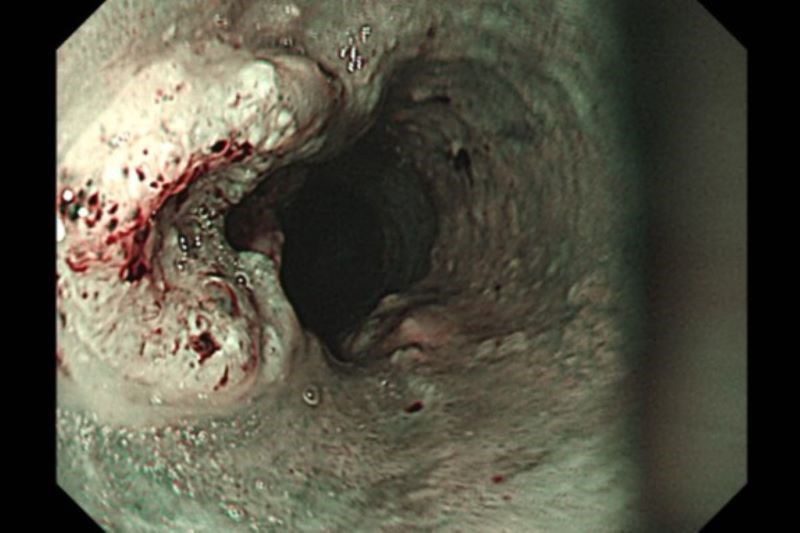

胃鏡影像下的食道內側,左側突起處為食道癌病灶。

胃鏡檢查是診斷食道癌最常見的方法,可直接觀察腫瘤並切片確認,並搭配電腦斷層、全身骨掃描、腦部磁振造影、全身正子攝影評估轉移情形。洪嘉聰醫師表示,食道癌治療會依期別與病灶範圍調整方式,以手術切除為優先考量。傳統開胸手術需於胸腹開15至20公分大傷口,易併發肺炎;若合併下咽癌,可能得進一步施行全喉切除與永久氣切,造成語音、進食與呼吸功能的永久改變。現今微創技術則可透過胸腔鏡、腹腔鏡完成,僅需胸腹數個1至2公分的小切口,並於頸部開4至5公分切口進行胃管上拉與頸部食道縫合重建,術後恢復較快。以張先生為例,雖合併下咽癌,但經放射治療後腫瘤縮小,最終經醫療團隊評估,食道癌以微創手術切除與重建,下咽癌持續以藥物治療,避免全喉切除與永久氣切,維持術後生活品質。但畢竟是切除縫合手術,部分病人會在術後出現滲漏或狹窄情形,須再接受擴張治療改善進食情況;此外,病人若有復發情況,或因高齡、共病不適合手術者,則會以化療、放療或免疫治療為主。